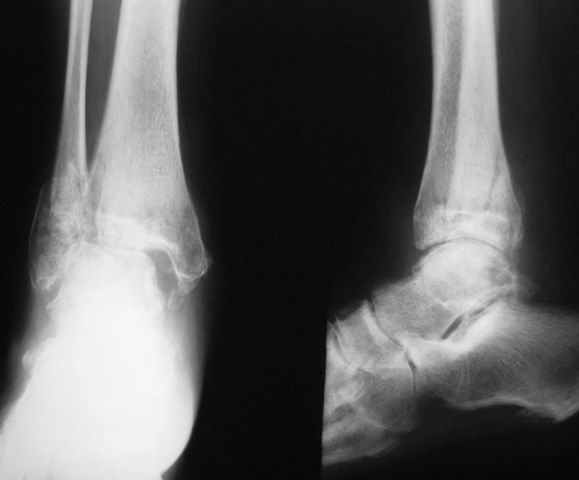

На прием обратилась женщина 50 лет с неправильно сросшимся переломом наружной лодыжки и наружным подвывихом стопы.

Травма в октябре 2009 года - подвернула стопу (на настоящий момент 6 месяцев): открытое повреждение правого голеностопного сустава: закрытый перелом наружной лодыжки с вывихом стопы кнаружи, разрыв дельтовидной связки (рана по внутренней поверхности около 8 см). При поступлении произведено вправление вывиха, трансартикулярная фиксация голеностопного сустава спицами и ПХО раны. Заживление раны осложнилось краевым некрозом, рана зажила вторичным натяжением. Около недели назад открылся свищ с серозно-гнойным скудным отделяемым. В настоящее время имеется отек, движения в голеностопном суставе резко ограничены, стопа в нейтральное положение не выводиться (угол около 5 градусов подошвенного сгибания), ходит (около 1 месяца) с частичной опорой, полная нагрузка болезненна.